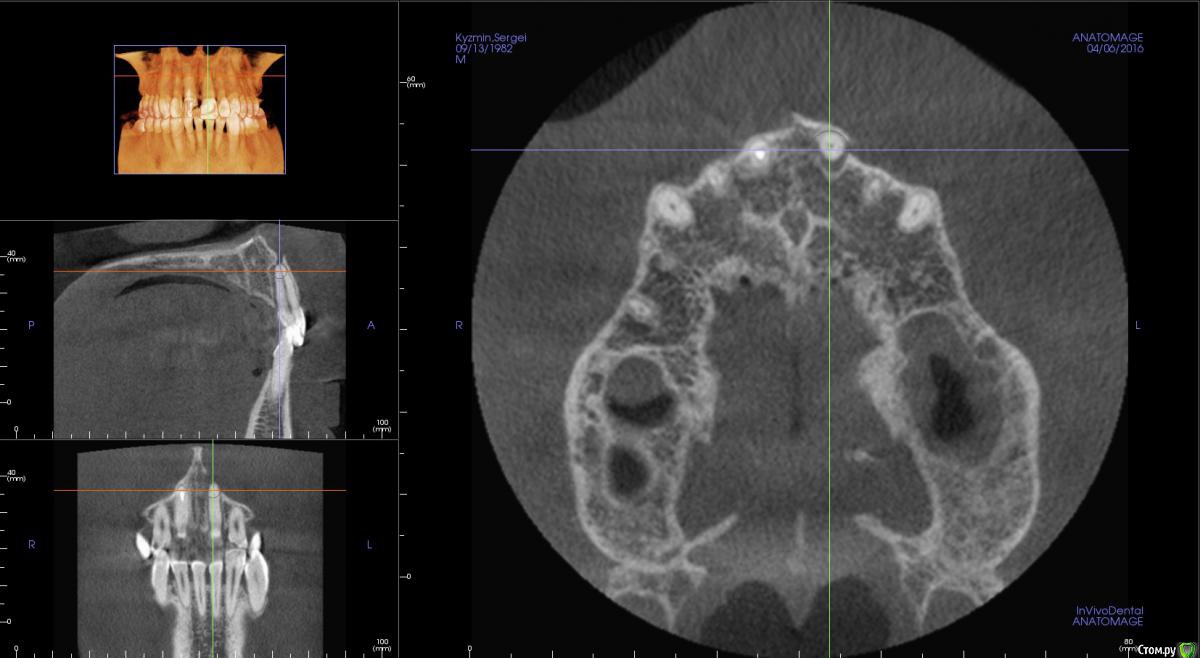

kamranchick Опубликовано 17 апреля, 2016 Поделиться Опубликовано 17 апреля, 2016 Пришел пациентДок привет, что то зуб шатается, можно ли его оставить, вот такие дела)как бы вы поступили бы? Ссылка на комментарий